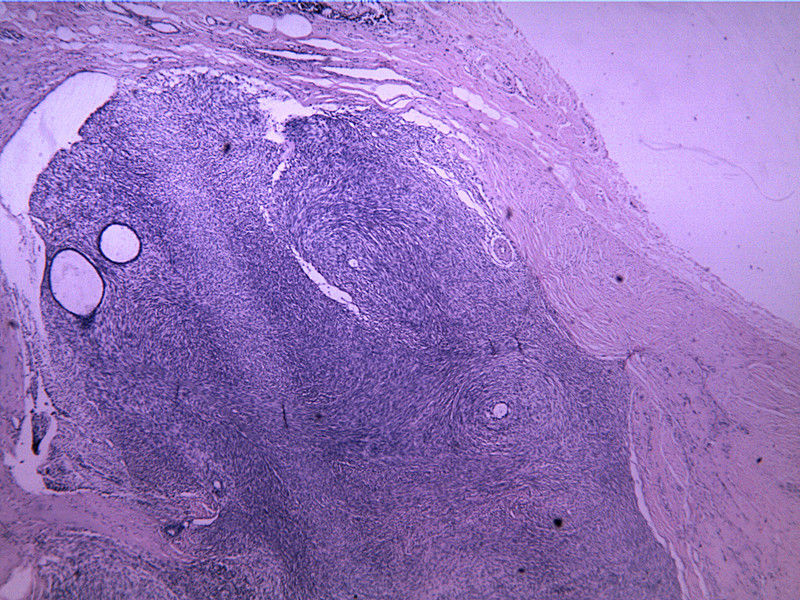

B3817

包块-有包膜(V3x3x2,39y)

图4

叶状肿瘤 导管周间质肿瘤